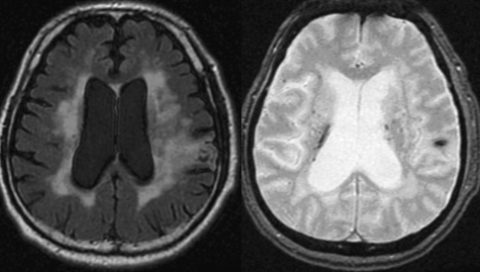

例えば、脳血管系の病棟なら急変で多いのは意識障害である。この状態で必要な流れは、意識状態の把握やバイタルサイン測定、医師への報告である。そこから医師の診察や画像検査で異常が見つかれば手術や処置が行われるため、看護師はその準備が必要になる。